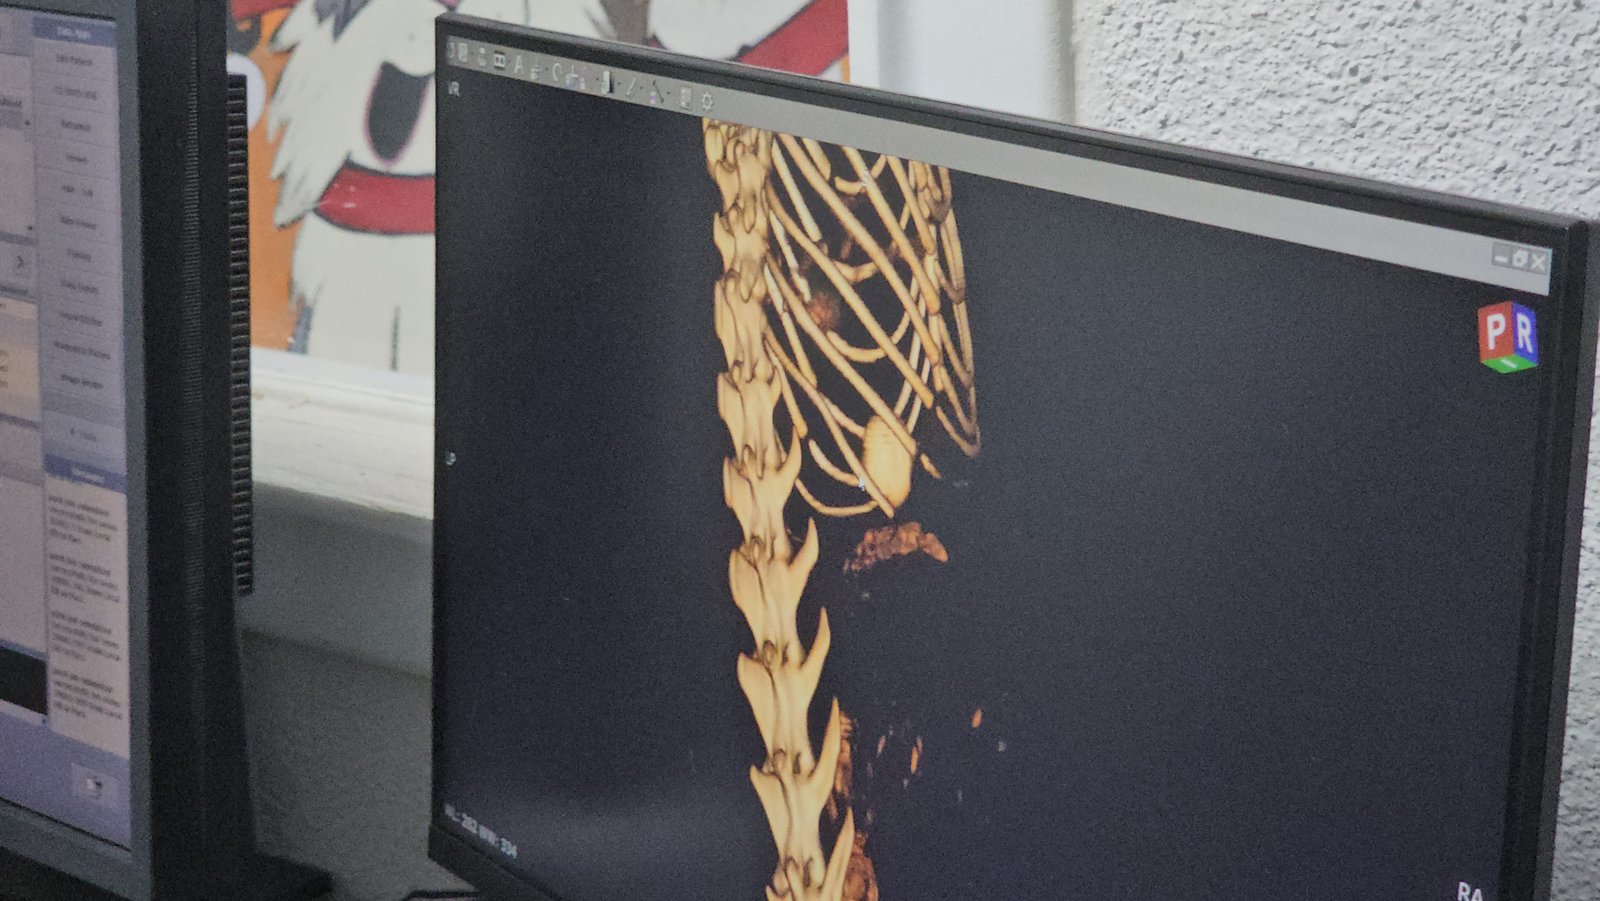

Zonguldak’ta, 5 yaşındaki ‘Mustafa’ isimli kedi 4 yıldır devam eden kusma şikayeti nedeniyle sahipleri tarafından özel bir veteriner kliniğe götürüldü. Burada tomografi çekilen kedinin midesinde dolap veya camlara yapıştırılan vantuzlardan biri olduğu tespit edildi. Endoskopi yöntemiyle vantuz, kedinin midesinden çıkarıldı. Yapılan gözlemde kedinin kusma şikayetinin geçtiği anlaşılınca sahibine teslim edildi. Vantuzun mideye verdiği zarar nedeniyle de ilaç tedavisine başlandı.

Operasyonu yürüten Veteriner Hekim Ömer Faruk Alkan, yerde bırakılan toka, ip gibi küçük nesnelerin kedi sahipleri için dikkat edilmesi gereken şeylerden olduğunu belirterek, “4 yıldır kusmasına sonuç, cevap alınamamıştı. Röntgenlerde hiçbir sıkıntı yoktu, bütün testleri çok iyiydi. Hiçbir problemi yoktu ama 2 günde 1 kusma şikayeti vardı. Çektiğimiz tomografide, çocuğun midesinde 4 yıldan beri kalan buzdolabı yapışkanlarından vantuzlarından olduğunu gördük. Ameliyatsız bir şekilde, endoskopi ile mideden çıkarttık. Şu an kusması tamamen kesildi. Herhangi bir kusmamız yok. Çocuk 4 yıl sonra ilk kez kusmadığı 2 günü arka arkaya yaşadı. Kusmayacak gibi gözüküyor. Burada vantuzun mideye verdiği zararlar var, mide duvarında kalınlaşma gibi onların tedavisini yapacağız. İnşallah Mustafa bundan sonraki hayatına kusmadan devam edecek. Mustafa 5 yaşında, 1 yaşından beri kusuyor. Yavruyken yemiş. Kedi sahipleri için de en önemli kısım bu, yerde toka, ip bu şekilde vantuz bulundurmamaları gerekiyor. Kedi yiyebiliyor. Mustafa şanslı olanlardan, bağırsaklarına inmemiş tıkama yapmamış. Bağırsaklara inip tıkama yaptığında daha ciddi komplikasyonlara, ölüme sebep olabiliyor” dedi. (DHA)